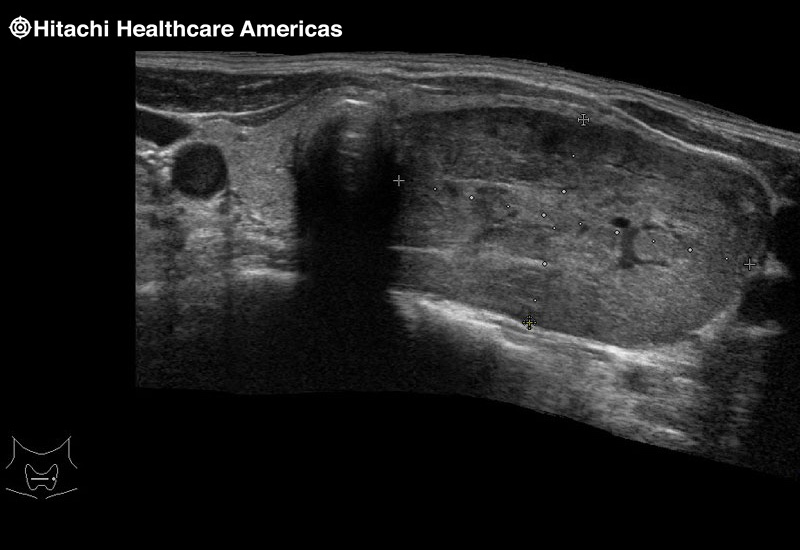

Superior guidance for all applications

Fujifilm Healthcare Americas is committed to designing tools that help surgeons navigate inside the human body and provide the necessary information to immediately make critical surgical decisions.

Fujifilm Healthcare's dedication to Surgeons provides outstanding ultrasound technology, professional support and the specialized tools necessary to best perform comprehensive real-time ultrasound imaging in Breast Surgery, General Surgery, Laparoscopic Surgery, Neurosurgery, Robotic Surgery and Surgical Oncology.

A critical function of robotic ultrasound guidance is tumor margin identification. Fujifilm's family of robotic probes all have the optimum location of the attaching mechanism that allows for full wrist articulation of the probe. The result is an increased confidence that the tumor margins have been completely identified.

Imaging Clearly Defined

State-of-the-art digital architecture and advanced imaging features to redefine the capabilities of surgical ultrasound.